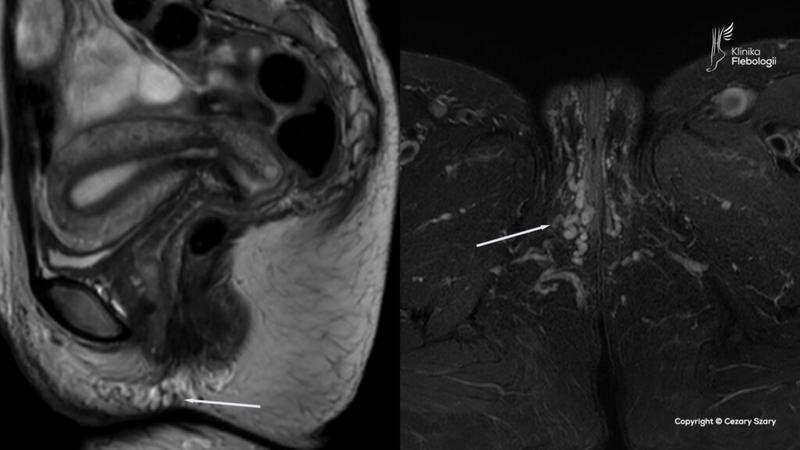

1. Diagnostyka: Zanim przystąpisz do jakiejkolwiek interwencji, konieczne będzie wykonanie diagnostyki. Proces ten obejmuje badanie fizykalne, które pomoże ocenić stan naczyń żylnych. Lekarz często zaleca USG Doppler, aby sprawdzić przepływ krwi w żyłach sromu. Ponadto, w celu zlokalizowania potencjalnych problemów z krążeniem, mogą być potrzebne dodatkowe badania, takie jak angio-CT czy flebografia. Odpowiednia diagnostyka pozwoli lekarzowi dobrać najbardziej skuteczną metodę leczenia.